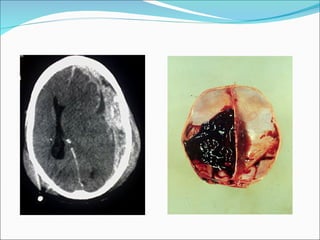

HEMATOMA EPIDURAL AGUDO Ruptura arteria  meníngea media. Se suele asociar con fracturas de cráneo, sobre las áreas  que cruzan los surcos de la AMM  75% de los hematomas epidurales ocurren en la región escamosa del hueso temporal .

HEMATOMA EPIDURAL

CLINICA Pérdida de conocimiento seguida por un período lúcido. Si hematoma crece aumenta la presión y puede originarse herniación del lóbulo temporal y compresión del tallo cerebral. El tratamiento es quirúrgico inmediato, con muy buen pronóstico si se interviene de forma precoz.  El pronóstico variará dependiendo de la situación del paciente antes de ser operado y de la precocidad de la evacuación quirúrgica. A mayor gravedad y mayor retraso en la cirugía, menos posibilidades de supervivencia.